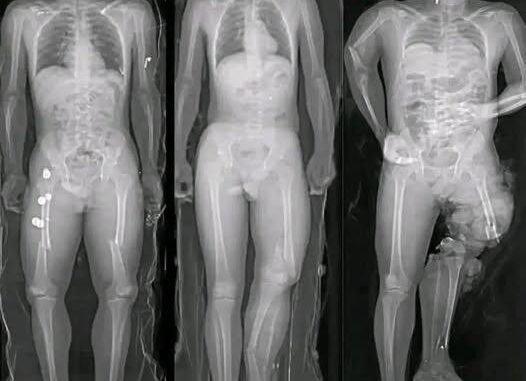

Medical research has identified a small number of myocarditis cases—an inflammation of the heart muscle—following certain mRNA vaccines, particularly among adolescent and young adult males. However, context is critical. These cases are rare, typically mild, and most individuals recover fully with minimal treatment.

Multiple peer-reviewed studies show that the risk of myocarditis from COVID infection itself is significantly higher than the risk associated with vaccination. COVID-19 as a disease has been linked to more severe cardiac complications, including inflammation, blood clots, and long-term heart damage.